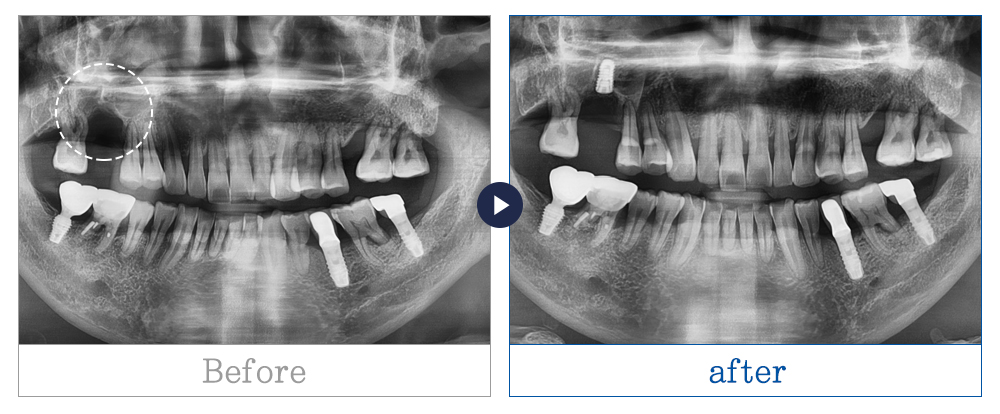

임플란트 사례

치료기간 3개월 이상

* 환자의 상황, 상태, 치료 계획마다 치료 기간은 상이할 수 있습니다